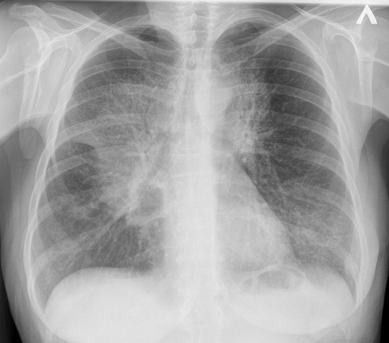

Рентгеноскопия органов грудной клетки

Рентгеноскопия органов грудной клетки в

онкологической практике применяется как дополнительный метод исследования в

дифференциальной диагностике центрального рака легкого: чем хуже пульсация

пораженного корня легкого, тем менее вероятна его сосудистая патология и более

вероятна опухолевая природа изменений.

Врачи-рентгенологи могут применять

рентгеноскопию грудной клетки при периферических образованиях в легких, если

таковые видны только на прямой рентгенограмме, но не определяются в других

проекциях - для выбора оптимального среза линейной томографии.

Рентгенография легких, норма

Рак легких